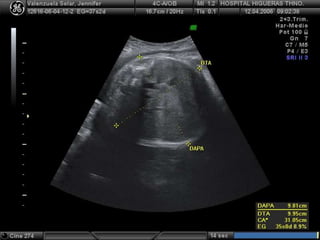

DAAP DAT CA

¿ QUÉ MEDIR ?

CC LF

+ EPF

CA = (DAAP + DAT) x 1,57

DAAP

DAT

ESTÓMAGO